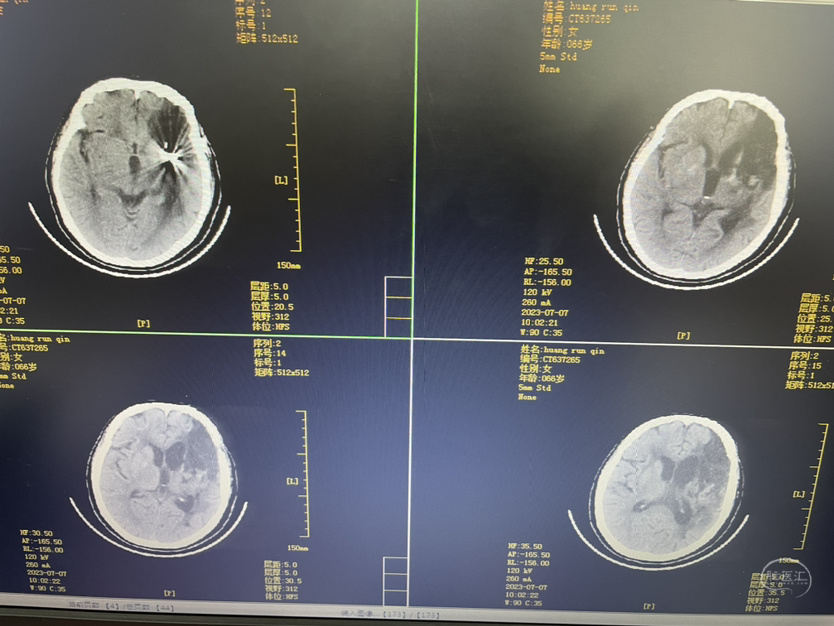

介入栓塞术后两个月来复查!患者清醒轮椅而来,言语稍含糊,右侧下肢肌力可大于三级,上肢一级!